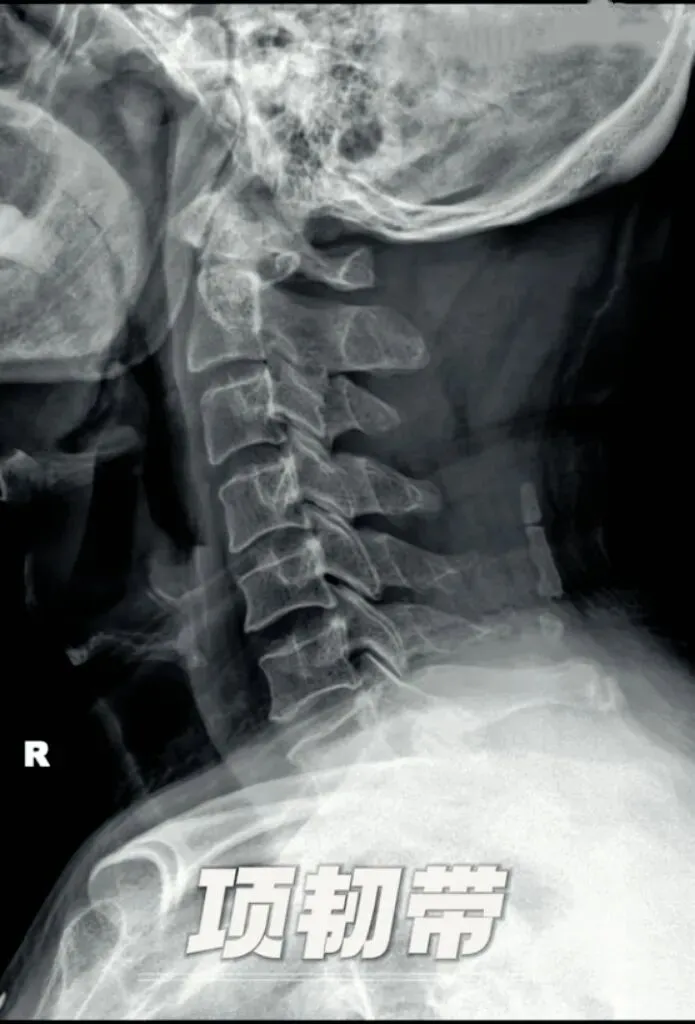

四,韧带钙化。颈椎的韧带有很多条,虽然X线无法直接显示颈椎韧带,但是我们可以通过解剖结构中韧带的走形区来间接判断。韧带钙化的原因诸多,主要从颈椎侧位片上进行观察。我们来学习几个常见的颈椎韧带钙化。首先是项韧带,位于枕外隆凸,枕外嵴、寰椎后结节及第二至第七颈椎棘突之间,

主要功能是限制颈部过度前屈,维持颈部姿势稳定,也是最常见的颈椎韧带钙化之一,多发生于颈4至6椎体的后方。